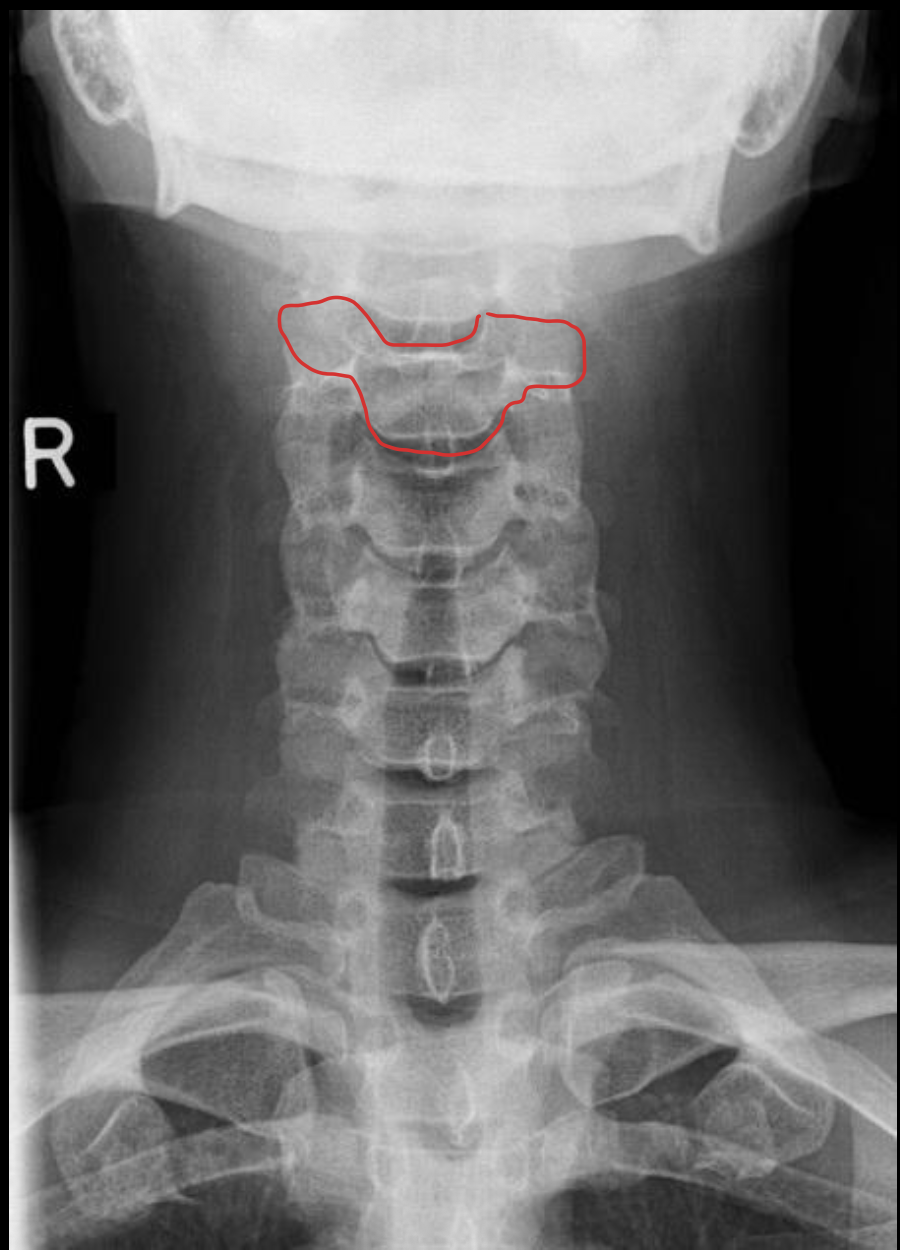

钩突

Uncinate process

关节柱 / 侧块

Articular pillars

棘突

Spinous process

乳突气房

Mastoid air cells

下颌角

Angle of mandible

椎间隙(Intervertebral Disc space)

IVD space

气管

Trachea